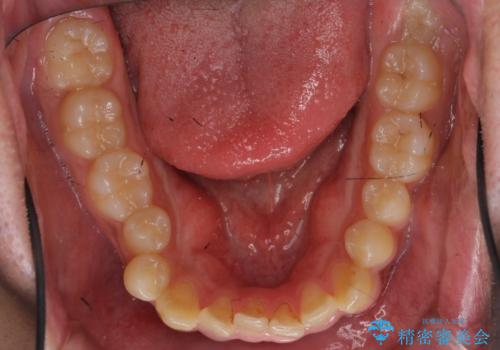

骨格性の受け口 非抜歯で下の歯を後ろに下げる インビザラインで インプラント矯正

- 受け口を主訴に来院。

一見簡単そうにみえて、前歯の反対咬合を入れ替える際は一時的に奥歯もかみ合わない状態になります。

顎のずれが大きい場合はそれだけでは治療できないことが多いです。

当院では下の歯を後ろに下げるため矯正用ミニスクリューを用いてしっかり移動を行う等ご説明をし、治療開始しました。